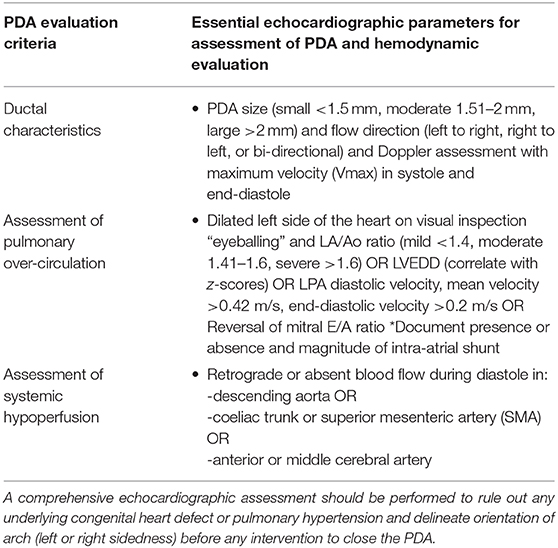

The echocardiography is the gold standard bedside investigation to diagnose PDA. In addition to make a confirmative diagnosis of PDA and exclude/diagnose any associated congenital heart defect (CHD), it can help in estimating the magnitude of shunt volume and assessing its hemodynamic significance—it can be used to assess the hemodynamic impact from pulmonary overcirculation and systemic hypoperfusion due to shunt volume (13–15). This could be systematically achieved by studying: (a) ductal characteristics, (b) parameters of pulmonary overcirculation, and (c) signs of systemic hypoperfusion (Figure 2).

Figure 2. Summary of an approach to echocardiographic assessment of PDA and hemodynamic evaluation; LA, left atrium; LV, left ventricle; DA, ductus arteriosus; Ao, aorta; SMA, superior mesenteric artery; ACA, anterior cerebral artery; MCA, middle cerebral artery; SVC, superior vena cava.

Based upon the clinical and echocardiographic criteria various staging systems been described and have been shown to help in decision making for intervention (17, 19). However, in authors experience they have not been widely adopted in the clinical practice which could be possibly because of their extensive number of parameters. Recently, van Laere et al. (13) suggested essential various echocardiographic parameters including measuring left ventricular output in all infants needing assessment of PDA. However, in authors experience these staging systems needing extensive echocardiographic parameters assessment have not been widely adopted in the clinical practice. We have summarized the commonly used parameters which would help the clinicians assessing the PDA and its hemodynamic significance on echocardiography, and in making clinical decisions in the clinical practice.

Clinical Decision Making: is the PDA Hemodynamically Significant?

The above echocardiographic parameters summarized in Table 1 may help in addressing the issue of whether the PDA is hemodynamically significant or not. However, the definition of an hsPDA continues to evolve. In addition to multiple echocardiographic indices described above, the hemodynamic significance of a persistent PDA should be interpreted by considering the gestational and chronological age, and by assessing the vulnerability of organs at risk for overflow (the lungs), or hypoperfusion (e.g., the brain, intestines, and kidneys). Further work is needed to reach a consensus on how to define and manage a hemodynamically significant persistent PDA in extremely preterm infants (34).

Table 1. Summary of essential parameters used for echocardiographic assessment and hemodynamic evaluation of PDA in ELGAN infants.